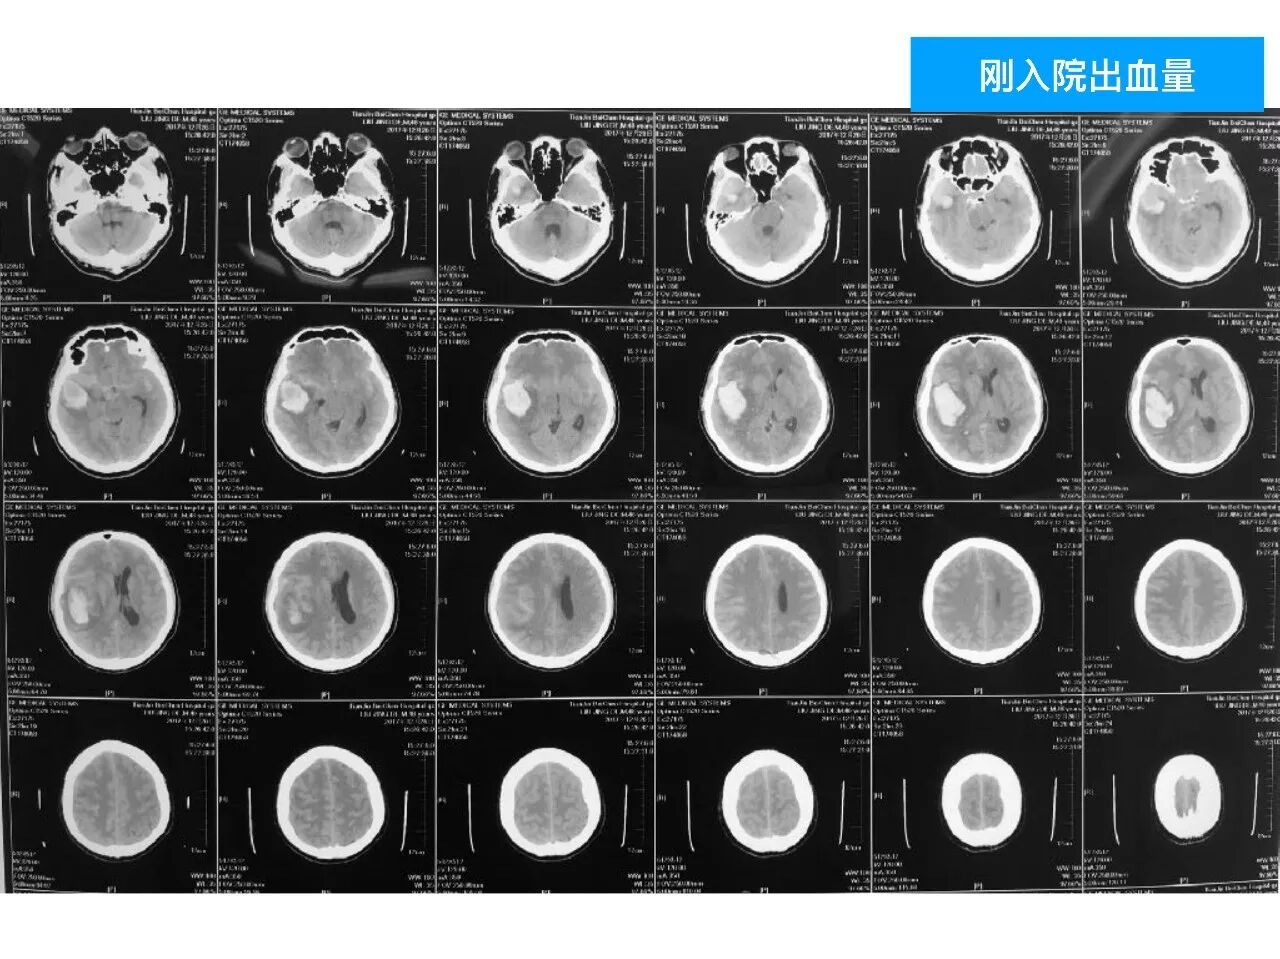

今天为大家分享的是《颅脑创伤-神经重症病例周刊》第四十九期,由天津市环湖医院神经外科五病区主任佟小光教授团队带来的:DAVF出血、脑疝急诊手术一例,欢迎阅读。

(1)DAVF引起如此严重的脑出血很少见,容易与普通脑出血混淆;

(2)DAVF即使术前很严重,及时闭塞DAVF,清除血肿,常常有好的预后;此例患者术前双侧瞳孔散大,术后回复超乎常规;